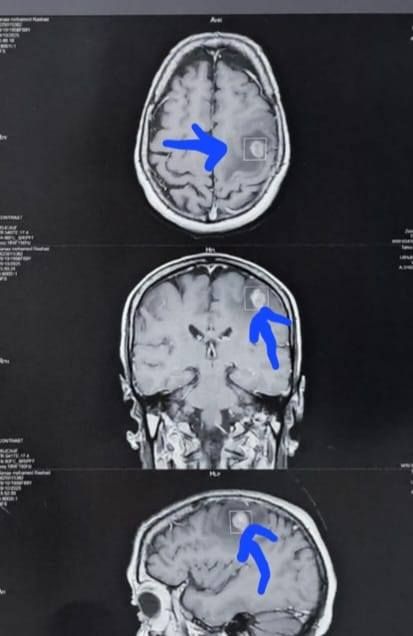

وكشف الدكتور إبراهيم الغريب رئيس قسم جراحة المخ والأعصاب بالمستشفى، أنه تعود تفاصيل الحالة إلى استقبال المستشفى المريضة بالعيادة الخارجية وهي تشكو من تنميل وضعف بالجانب الأيمن وثقل بسيط في الكلام، وبإجراء الفحوصات اللازمة من أشعة مقطعية ورنين مغناطيسي بالصبغة، تبين وجود ورم بالمخ، وتم إعطاؤها العلاج المناسب لحين استكمال الفحوصات.

أشعة المريضة

الأشعة الخاصة بالمريضة

الأشعة